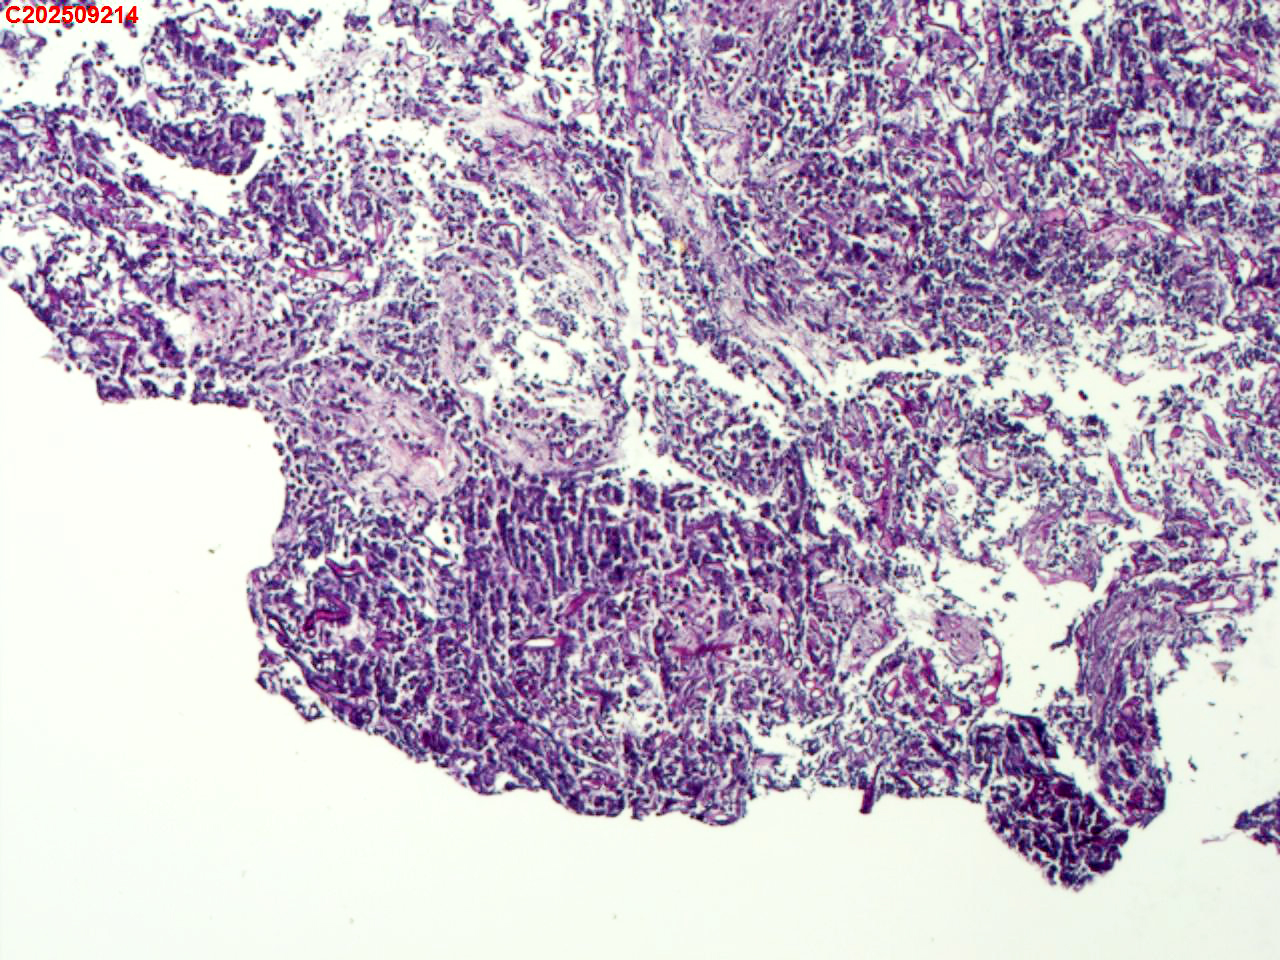

左肺下叶背段咬检组织

性别年龄59岁临床诊断肺结核?肺部感染?

一般病史胸部(平扫):两侧胸廓对称,气管及纵隔居中。双肺纹理增多、紊乱,胸膜下区见多发索条影;双肺见多发大小不等斑片状高密度影,部分呈树芽征样磨玻璃样改变,部分病灶内见支气管含气、少许钙质沉积。气管及大支气管通畅。心脏大小形态可;冠状动脉走行处见多发条形高密度影。双侧胸膜局部肥厚粘连。纵隔内见多发淋巴结影,4L区较大者约10mm* 16mm。

标本名称左肺下叶背段咬检组织

大体所见纤支镜检查:左肺主支气管上叶、下叶及各段级支气管通畅,粘膜无充血,背段外亚段远端可见疑似白色痰栓,灌洗支气管刷检并镜下尝试活检钳清理,发现其质硬考虑为新生物并咬检,该部位深远,且咳嗽及呼吸干扰取材不理想。

毛霉菌病